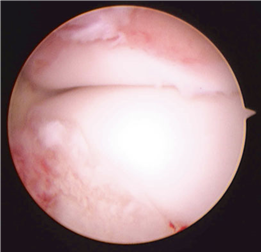

In cases of end-stage hallux rigidus, first MTP arthrodesis yields excellent, predictable outcomes. A dorsal longitudinal incision is made just medial to the EHL tendon. The joint is exposed, and aggressive cheilectomy is performed to remove all dorsal, medial, and lateral osteophytes. The remaining articular cartilage on the metatarsal head and the base of the proximal phalanx is resected using cup-and-cone reamers, which allow for infinite adjustment of the joint position prior to fixation.

For hallux rigidus, Coughlin and Shurnas developed the definitive clinical and radiographic grading system that remains the international standard for guiding treatment. Their research definitively proved that while cheilectomy provides excellent relief for Grades 1 and 2, first MTP arthrodesis is the only reliable, long-term solution for Grade 3 and 4 disease. These landmark studies form the bedrock of modern foot and ankle surgical training, ensuring that orthopedic surgeons approach first metatarsal pathology with a nuanced, evidence-based perspective.